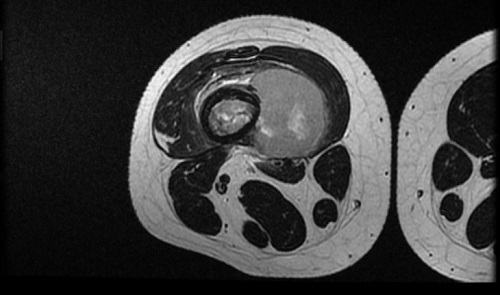

Se realiza traslado a hospital de referencia para ingreso en Unidad de Oncología. A su ingreso se amplía el estudio de la lesión realizando una resonancia magnética (Figs. 2 y 3) y estudio de extensión con tomografía computarizada pulmonar confirmándose la sospecha de tumor maligno óseo y metástasis pulmonares. Posteriormente se toma biopsia de dicha lesión guiada por ecografía confirmándose el diagnóstico de osteosarcoma.

| Figura 2. Resonancia magnética. Lesión agresiva medular ósea (10 cm de extensión cráneo-caudal) con masa de partes blandas paraostal (35 × 62 × 42 mm) que sobreeleva el periostio en fémur distal derecho |

|---|

![]() |